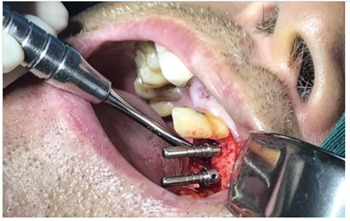

使用種植導(dǎo)板專用手術(shù)器械完成種植位點(diǎn)逐級備洞

進(jìn)行精準(zhǔn)測量

植體置入

愈合基臺的置入及縫合